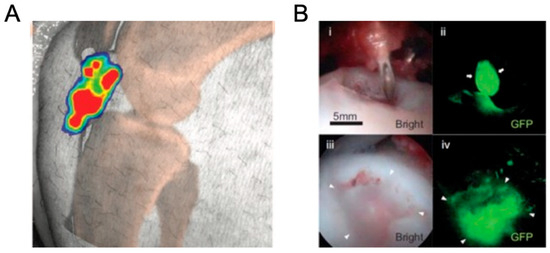

- Nakamura, T.; Sekiya, I.; Muneta, T.; Hatsushika, D.; Horie, M.; Tsuji, K.; Kawarasaki, T.; Watanabe, A.; Hishikawa, S.; Fujimoto, Y.; et al. Arthroscopic, histological and mri analyses of cartilage repair after a minimally invasive method of transplantation of allogeneic synovial mesenchymal stromal cells into cartilage defects in pigs. Cytotherapy 2012, 14, 327–338. [Google Scholar] [CrossRef]

- Takaku, Y.; Murai, K.; Ukai, T.; Ito, S.; Kokubo, M.; Satoh, M.; Kobayashi, E.; Yamato, M.; Okano, T.; Takeuchi, M.; et al. In Vivo Cell Tracking by Bioluminescence Imaging after Transplantation of Bioengineered Cell Sheets to the Knee Joint. Biomaterials 2014, 35, 2199–2206. [Google Scholar] [CrossRef]